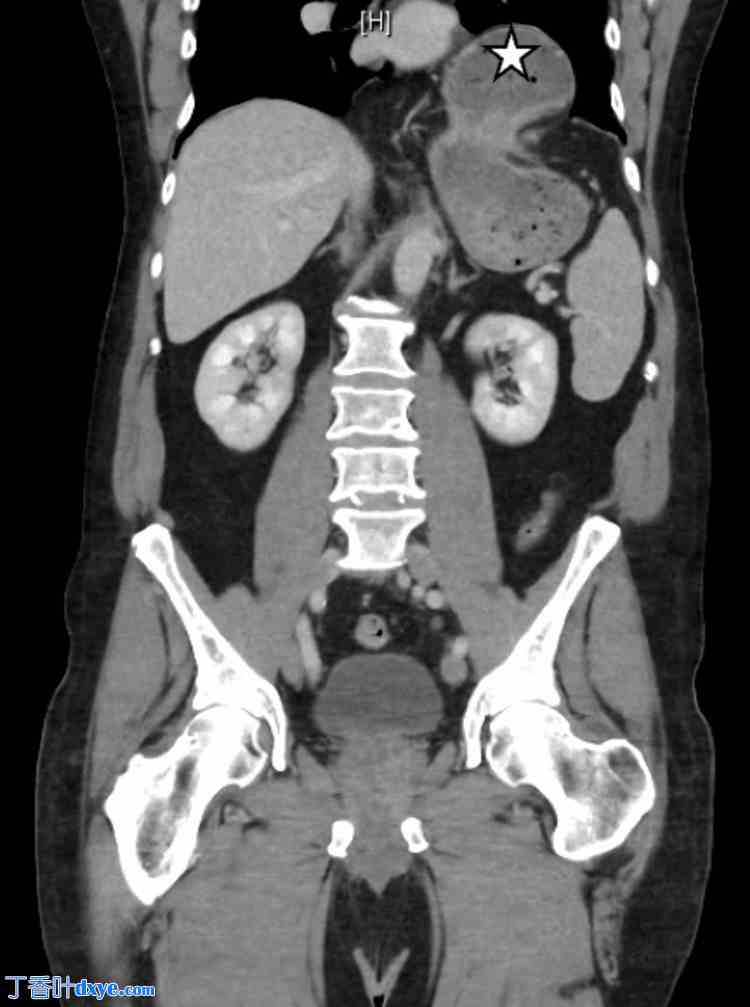

尽管住院第一天症状有所改善,但早餐后症状复发。尽管接受了止吐治疗,患者仍持续出现恶心和呕吐。置入鼻胃管进行胃减压。后续腹部X光检查显示明显的食管裂孔疝,大部分胃位于左半膈上方(图2)。钡剂食管造影显示一个大的滑动性食管裂孔疝,尽管患者禁食10小时,但胃内仍有液体和碎屑。钡剂食管造影也显示造影剂未从胃中排出,提示急性胃扭转(图3)。患者被诊断为嵌顿性食管旁疝和胃轴性胃扭转。

图3. 钡剂食管造影图像。

钡餐食管造影检查的连续图像。图像 A 和 B 显示食管裂孔疝,而图像 C 显示造影剂未从胃中排出,提示急性胃扭转。